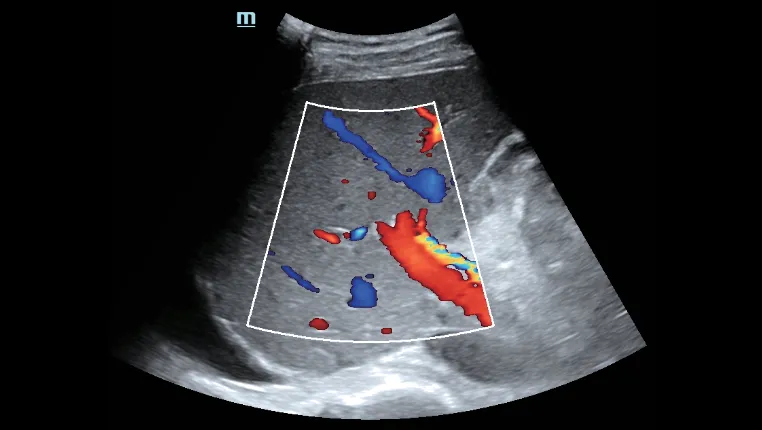

Advanced ViTE (визуализированная транзиторная эластография)

- Проводить количественное выявление и оценку фиброза и стеатоза печени под визуальным контролем 2D-ультразвука в режиме реального времени

- Позволяет избежать образования кровеносных сосудов и повреждений, повысить точность и достоверность измерения

- Превосходное ультразвуковое изображение и функциональность позволяют всесторонне оценить морфологию и гемодинамику печени.

Пункция печени под контролем ультразвука

Пункция печени под контролем ультразвука Асцит печени

Асцит печени Оценка портальной гемодинамики

Оценка портальной гемодинамики Оценка морфологии печени